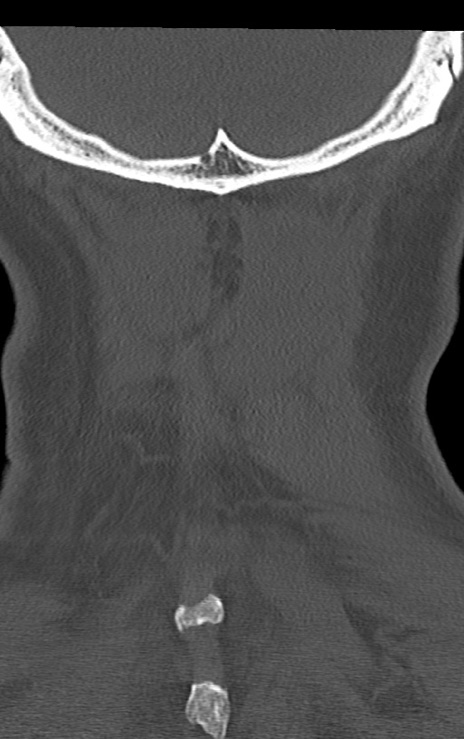

【整形】TIPS症例7 頚椎CT(冠状断像)

【症例】60歳代男性

【主訴】両手のしびれ

【現病歴】15年前より右手のしびれあり。4ヶ月前から左手のしびれあり。最近、症状増悪あり。

頚椎CT